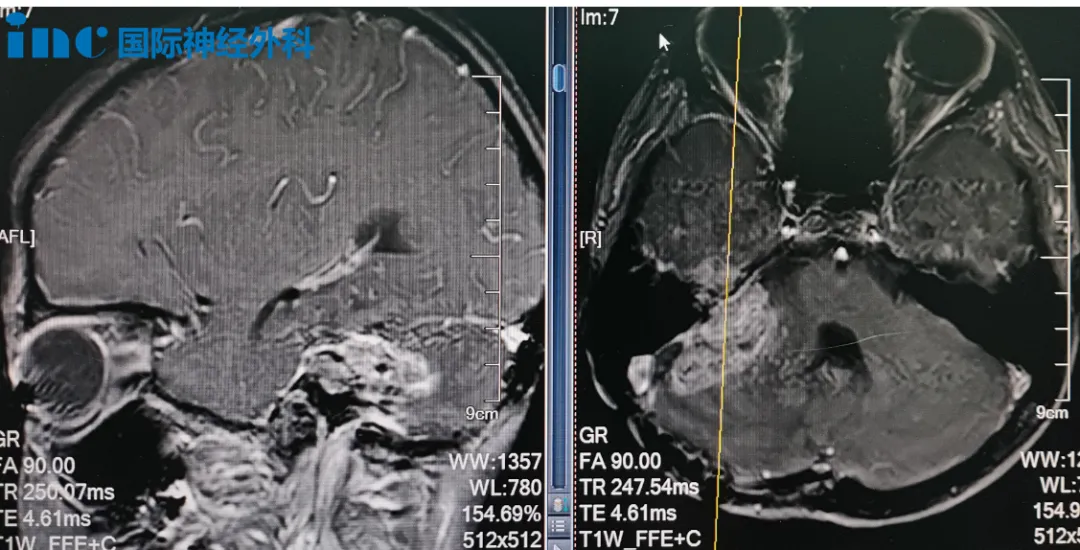

达恩的术前MRI

小正的术前MRI